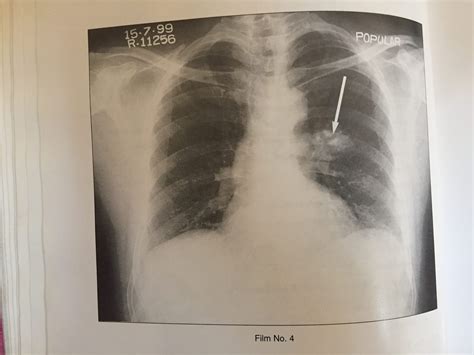

• Chest X-ray: A chest X-ray can reveal the presence of calcium deposits in the lungs.

• CT Scan: A computed tomography (CT) scan provides detailed images of the lungs and can help identify the location and extent of the calcification.